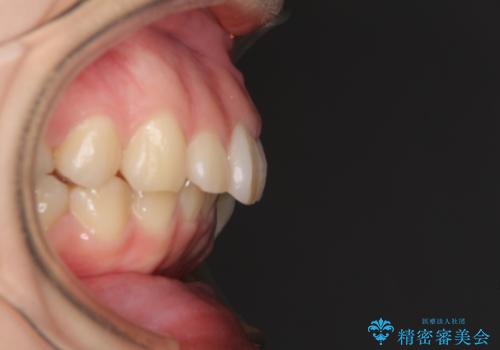

- 口元の突出感を気にして来院された患者様です。

上下左右の第一小臼歯4本を抜歯して口元を下げる治療計画としました。

非常に大きな虫歯のあった下顎大臼歯は、根管治療を行い、矯正治療後にオールセラミッククラウンにて補綴治療を行いました。

当初予定では3年以上かかるとお伝えしておりましたが、スムーズに歯列が整い、2年強で終了することができました。